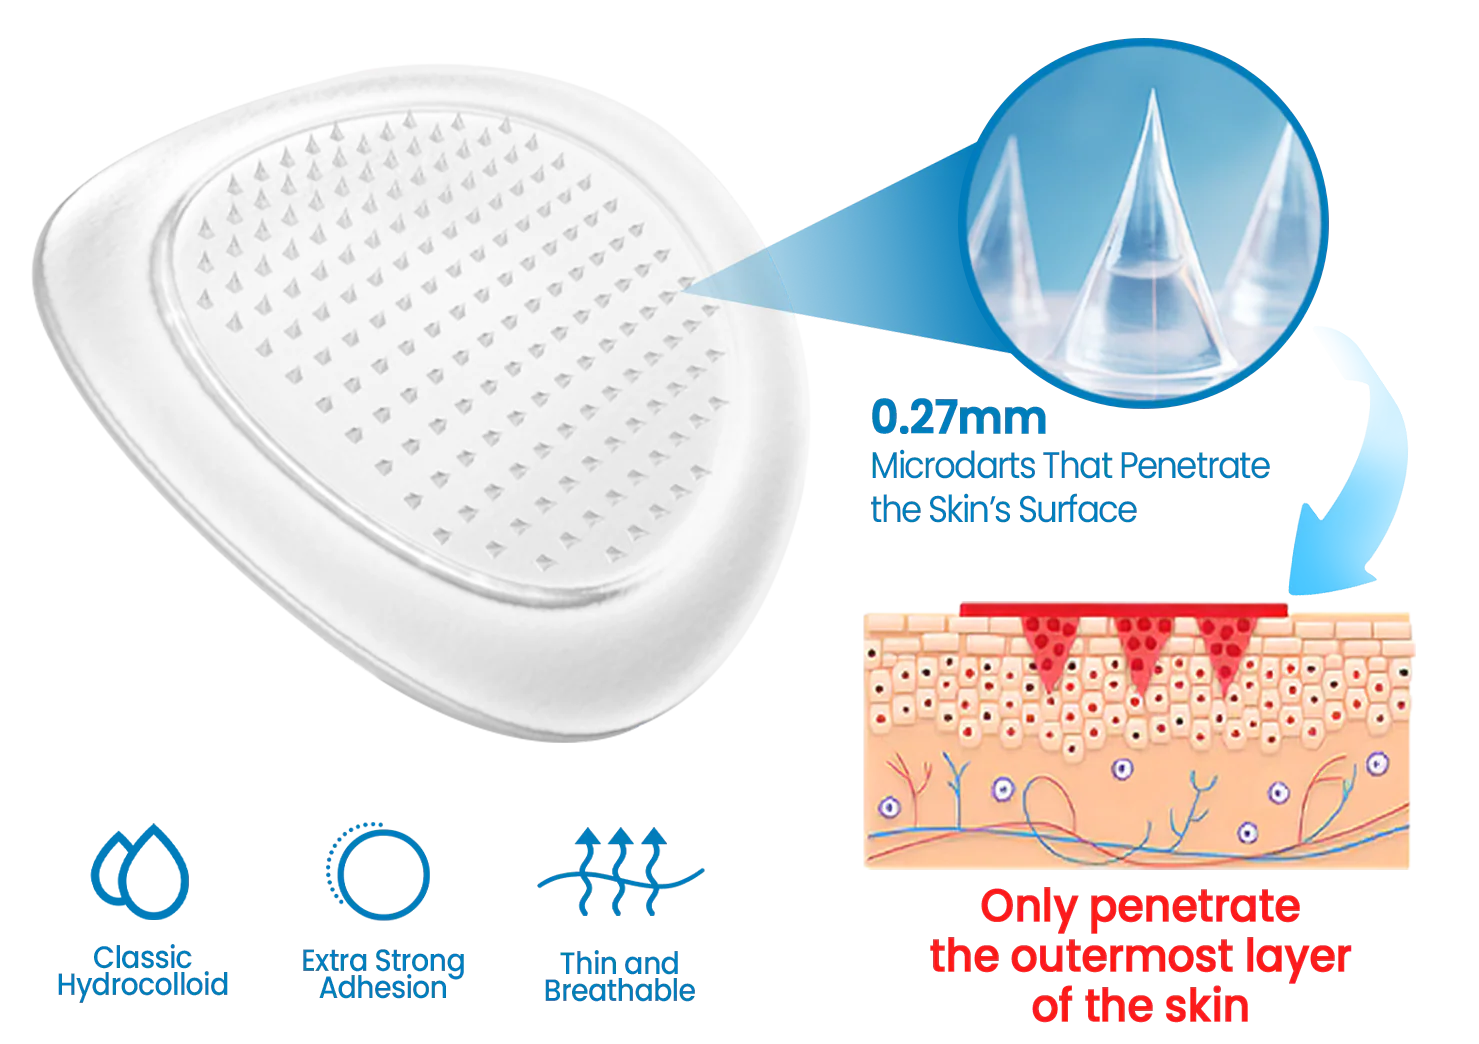

Each Alisanda® Microdart is just 0.27mm long — 10 times thinner than a needle. It penetrates only the skin’s outer barrier (stratum corneum), without reaching pain receptors or blood vessels.

➡ No pain, no bleeding — just deep, targeted delivery.

As the patch dissolves, the active ingredients penetrate the tissue — exactly where joint discomfort starts.